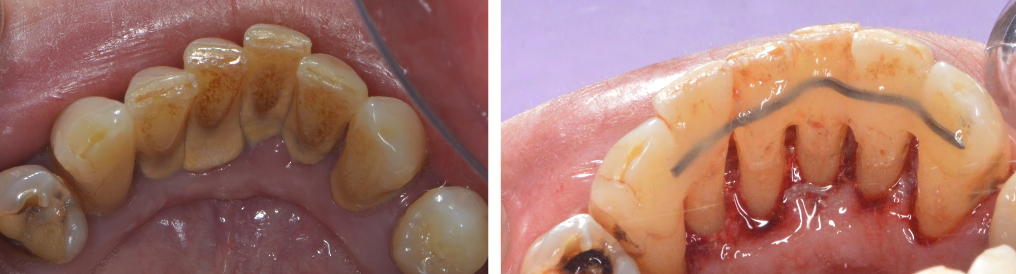

După terapia inițială și indicațiile de igienizare, medicul parodontolog vă va chema la reevaluare la 2-3 luni, pentru a vedea evoluția tratamentului. Este necesară această perioadă de pauză pentru a da timp organismului să reacționeze și să activeze mecanismele de regenerare, astfel se va observa eficiența terapiei și evoluția/involuția bolii. În cazurile în care nu se observă un progres substanțial, se va relua din nou terapia inițială, iar în cazurile recidivante se va asocia și o terapie chirurgicală pentru regenerarea tisulară. De asemenea dinții cu mobilitate crescută vor fi incluși într-o imobilizare prin unirea lor cu o bandă de sârmă sau fibră de sticlă pentru sporirea stabilității lor (Fig. 5.3.3).

În cazul din imagine (Fig. 5.3.4.), s-a realizat inițial tratamentul bolii parodontale, prin detartraje și surfasaje radiculare, asociat cu îmbunătățirea igienei personale. Ulterior, a urmat un tratament protetic fiind realizate coroane metalo-ceramice, ce au restabilit complet funcția masticatorie și estetică. Pacienta revine la cabinet periodic, la fiecare 4 luni, pentru control și igienizare.